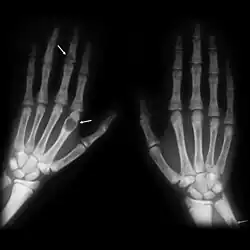

| Brown tumours of the hands in a patient with hyperparathyroidism. |

The brown tumor is a bone lesion that arises in settings of excess osteoclast activity, such as hyperparathyroidism. They are a form of osteitis fibrosa cystica. It is not a neoplasm, but rather simply a mass. It most commonly affects the maxilla and mandible, though any bone may be affected.[1] Brown tumours are radiolucent on x-ray.